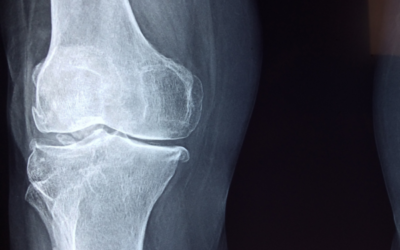

Arthritis? That’s just right…

Sitting too long can lead to neck pain, back pain, even knee pain. Great... They found arthritis. Many people who are diagnosed with...